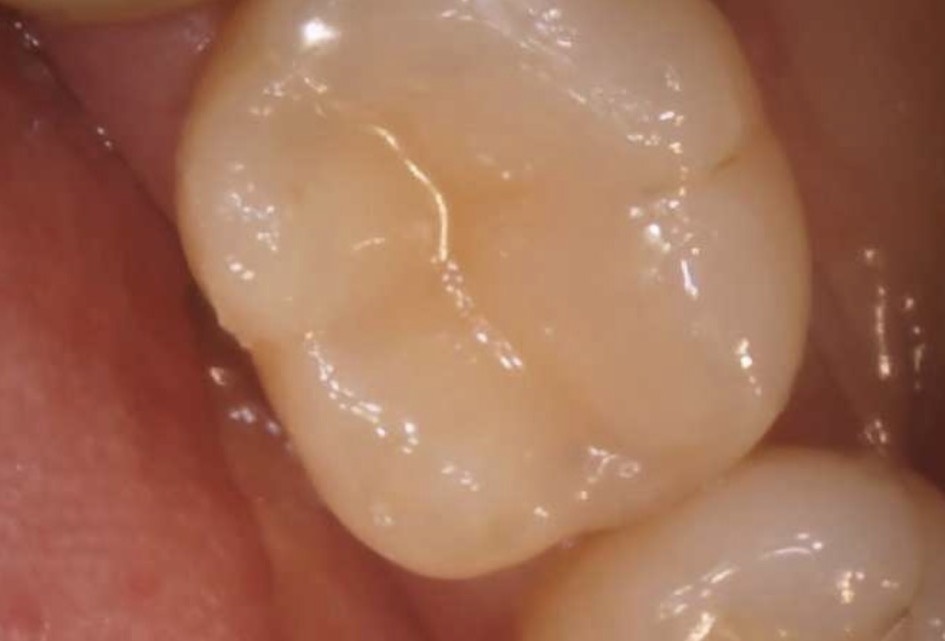

| 主訴 | 左下の奥歯の銀歯が取れた。 |

|---|---|

| 所見 | 下顎左側第一大臼歯咬合面二次う蝕 |

| 診断 | 下顎左側第一大臼歯咬合面う蝕1度 |

| 治療内容 | コンポジットレジン修復 |

| 治療後経過 | 痛みなく、咬合状態も良好。 |

| 治療期間 | 1回 |

| 治療費用 | 保険診療一本で1500円程度。 |

| リスク・副作用 | 今後も材料の経年劣化によって摩耗による着色や破折する可能性があると伝えた。 |